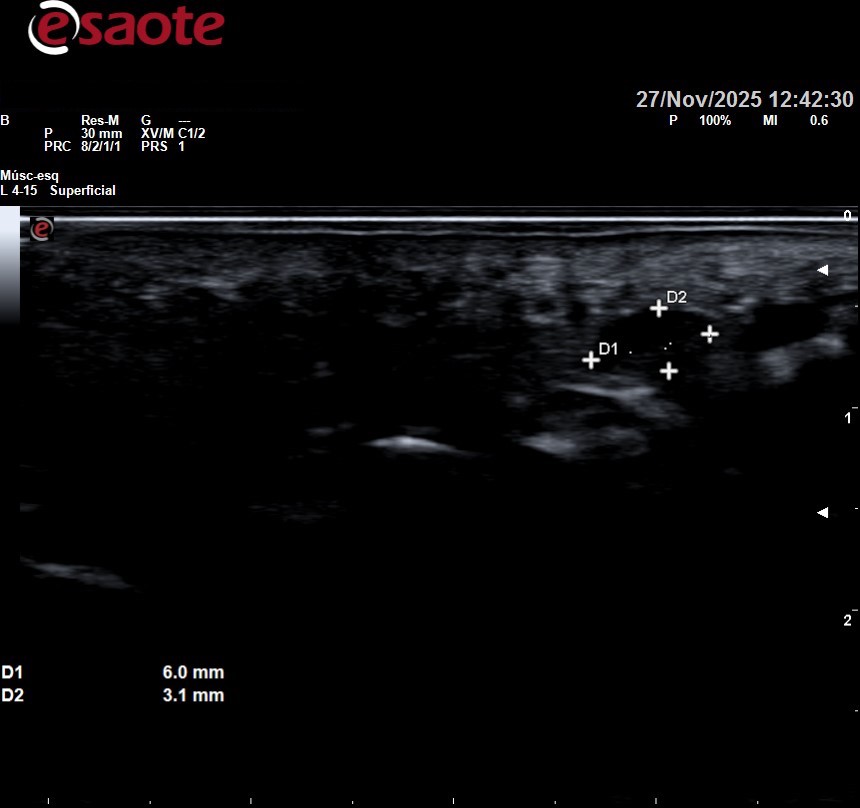

Imagenes ecográficas normales y de un neuroma de morton

Se puede observar arriba la ecografía de una paciente con neuroma de morton entre tercer y cuarto metatarsiano sintomatológico, que posteriormente se infiltró. Se observa como desde lo metatarsianos hacia los dedos el nervio se va haciendo más gordo. En la foto de abajo a la derecha lo vemos a lo largo en esa zona negra circular que se observa de la mitad de la imagen hacia la izquierda.